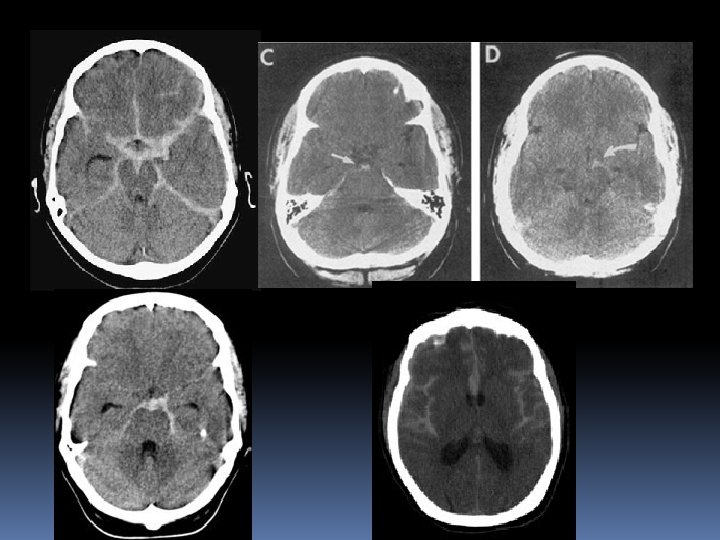

Intracranial Hemorrhage Intraventricular Hemorrhage Accounts for 3% of all non-traumatic ICH Hypertension is the most common etiology Often results from an intraparenchymal hemorrhage that extends into the ventricular system S/S: Headache, N/V, Progressive deterioration of consciousness, raised ICP, Nuchal rigidity Survivors may develop post-hemorrhagic hydrocephalus

Intracranial Hemorrhage Intraparenchymal Hemorrhage Basal Ganglia Hemorrhage Contralateral hemiparesis, hemichorea, hemisensory loss, and hemi -neglect are common neurological deficits Putaminal Hemorrhage is the most common location of intraparenchymal hemorrhage secondary to HTN Putaminal Hemorrhage, if massive, will result in Uncal Herniation (Ipsilateral blown pupil, contralateral hemiparesis, depressed LOC Caudate Hemorrhage is most likely to rupture into ventricles

Intracranial Hemorrhage Intraparenchymal Hemorrhage Thalamic Hemorrhage Contralateral hemiparesis, hemisensory loss and depressed LOC (wake center) are common deficits Extension into ventricular system common resulting in obstructive hydrocephalus with 3 rd ventricular enlargement => Parinaud’s Syndrome (Paralysis of voluntary upward gaze, light-near dissociation, convergence-retraction nystagmus, eyelid retraction)

Intracranial Hemorrhage Intraparenchymal Hemorrhage Pontine Hemorrhage Abrupt onset of coma, pinpoint pupils, autonomic instability, horizontal gaze paralysis, and quadriparesis The miotic pupils and depressed LOC may mimic opiate overdose

Intracranial Hemorrhage Lobar Intraparenchymal Hemorrhage This is often a clinically silent lesion S/S depend on location of hemorrhage, though hemiparesis, aphasia, hemianopsia, and hemisensory loss common Mimics lobar AIS